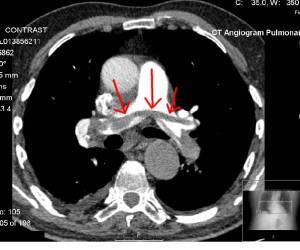

Header Image: IV contrast enhanced CAT scan showing Saddle Embolus (Red Arrows blood clot) lodged across bifurcation of pulmonary artery, Transferred from en.wikipedia to Commons. Author Glitzy queen00 at English Wikipedia. public domain. wikimedia commons.